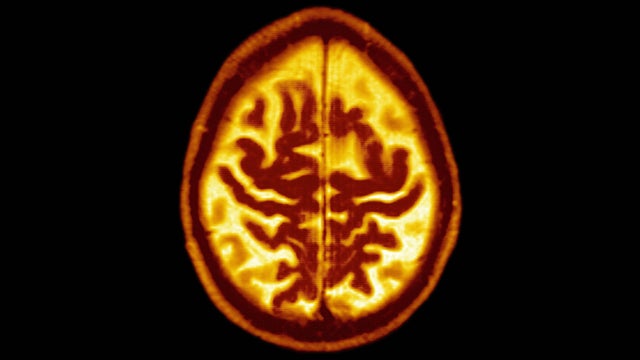

Intensive lowering of blood pressure, to a less than 120 mm Hg level, can have a measurable impact on mild cognitive impairment (MCI) -- a well-established precursor of dementia, a new study finds.